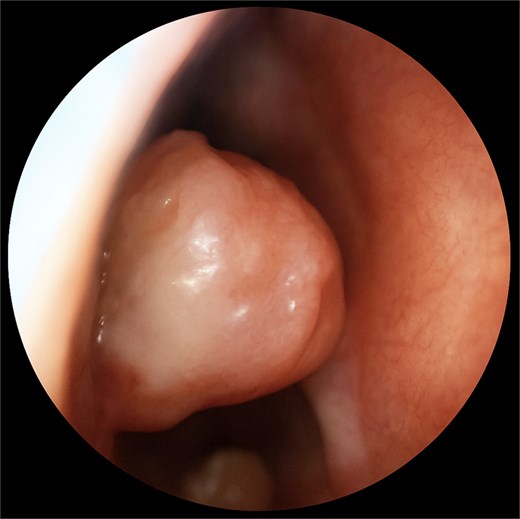

A 67-year-old male presented to our outpatient office with complaints of increasing bouts of right sided nasal bleeding for the preceding twelve months. He had been able to control the epistaxis with pressure and oxymetazoline nasal spray; however, a recent Emergency Room visit for persistent nasal bleeding prompted a referral to our office. The patient denied nasal trauma or other sinonasal problems in the past or present. He was not taking any anticoagulant or antiplatelet therapies. Nasal endoscopy revealed a soft, pale, non tender mass on the caudal end of the right inferior turbinate. Coagulated blood was noted over the anterior portion of this mass, without any vascular prominence or bleeding appreciated over the septal wall. This indicated the nasal mass was the site of recurrent epistaxis. Non-contrast computed tomography (CT) of the sinuses (Figs 1 and 2), showed a soft tissue prominence at the same area seen on endoscopy (Fig. 3).

Coronal non-contrast CT scan images of soft tissue lesion on right inferior turbinate.